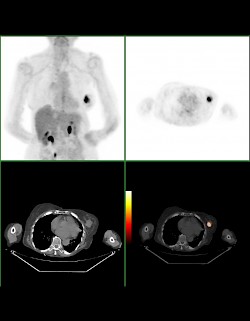

Das Besondere an der PET: Man erfährt, wie aktiv der Stoffwechsel in bestimmten Geweben des Körpers ist. Bei der PET arbeitet man mit einem Trick: der radioaktiv markierte Stoff – häufig wird Fluor benutzt – wird an Traubenzucker gekoppelt, der wie ganz normaler Traubenzucker aus dem Blut in die Zellen aufgenommen und zur Energiegewinnung genutzt wird. Damit kann man gerade Zellen oder Gewebe, die viel Energie verbrauchen und eine hohe Stoffwechselrate haben, auf Bildern sichtbar machen. Dies gilt vor allem für Gehirn- und Herzmuskelzellen, für entzündetes Gewebe, aber auch für Tumorgewebe. Gewebe mit schnellem Stoffwechselumsatz und hohem Zuckerverbrauch erscheinen auf schwarz-weiß-PET-Aufnahmen als besonders dunkle Flecken, auf Farbbildern als besonders leuchtende Flecken.

Heute wird ein PET-Scanner sehr häufig mit einem Computertomografen in einem Gerät kombiniert. Während die PET Auskunft über die Stoffwechselaktivität des untersuchten Gewebes gibt, erlaubt die gleichzeitig durchgeführte Computertomografie eine genauere anatomische Zuordnung des Befundes als die PET alleine.